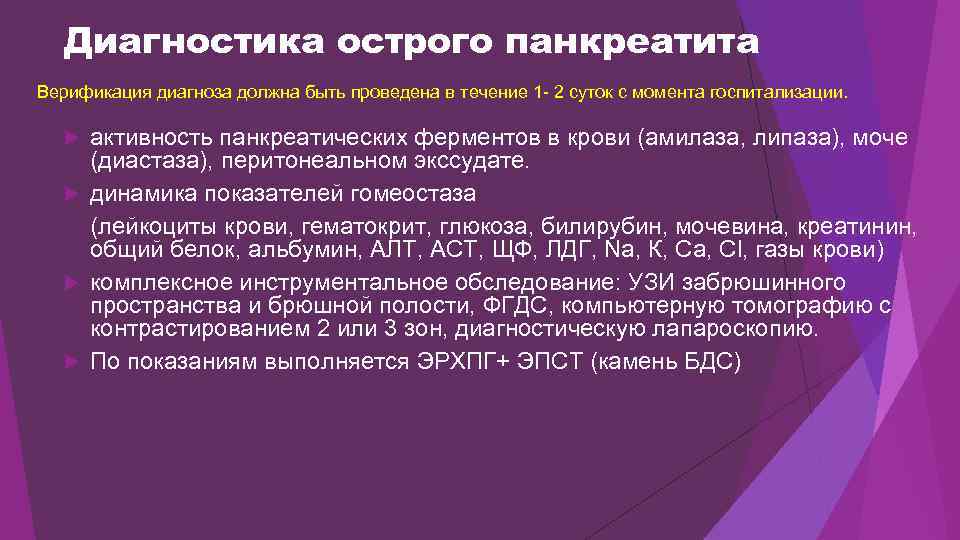

Диагностика острого панкреатита Верификация диагноза должна быть проведена в течение 1 - 2 суток с момента госпитализации. активность панкреатических ферментов в крови (амилаза, липаза), моче (диастаза), перитонеальном экссудате. динамика показателей гомеостаза (лейкоциты крови, гематокрит, глюкоза, билирубин, мочевина, креатинин, общий белок, альбумин, АЛТ, АСТ, ЩФ, ЛДГ, Na, К, Са, Сl, газы крови) комплексное инструментальное обследование: УЗИ забрюшинного пространства и брюшной полости, ФГДС, компьютерную томографию с контрастированием 2 или 3 зон, диагностическую лапароскопию. По показаниям выполняется ЭРХПГ+ ЭПСТ (камень БДС)

Диагностика острого панкреатита Верификация диагноза должна быть проведена в течение 1 - 2 суток с момента госпитализации. активность панкреатических ферментов в крови (амилаза, липаза), моче (диастаза), перитонеальном экссудате. динамика показателей гомеостаза (лейкоциты крови, гематокрит, глюкоза, билирубин, мочевина, креатинин, общий белок, альбумин, АЛТ, АСТ, ЩФ, ЛДГ, Na, К, Са, Сl, газы крови) комплексное инструментальное обследование: УЗИ забрюшинного пространства и брюшной полости, ФГДС, компьютерную томографию с контрастированием 2 или 3 зон, диагностическую лапароскопию. По показаниям выполняется ЭРХПГ+ ЭПСТ (камень БДС)